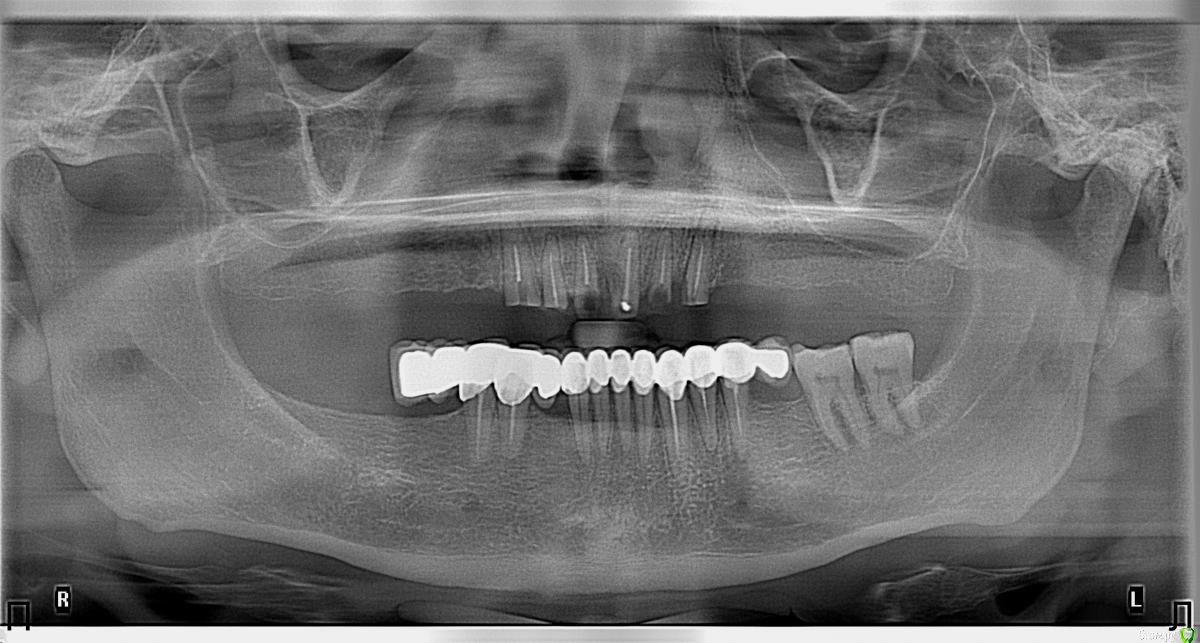

Nitrino1 Опубликовано 6 февраля, 2017 Поделиться Опубликовано 6 февраля, 2017 (изменено) Здравия желаю коллеги) Нужен совет опытных коллег, так как сам еще мало имею опыта в таких работах) Из анамнеза, был фронт мк, сначала расцементировка с одной стороны, и далее сломались зубы как видно на фотках. Хочет сохранить фронт своими зубами. Я посмотрел, как мне показалось реально вырулить если создать феррул в 2 мм. А после клыков уже имплантами восстаналивать. На данный момент перелечиваю 13й, попытался создать феррул в 2мм, на фотке можете увидеть. Как вы считаете, иду к успеху или к провалу? Что посоветуете?Вопросы:1. Беспокоит ситуация с 23им зубом, точнее с его апроксималкой (смотри ОПТГ), как поступить? Есть шанс сохранить зуб?2. Если получится сделать мост с 13-го зуба по 23-й зуб, тогда как поступить? Сделать вкладки , далее мк. А потом уже переходить к имплантам? Просто до завершения лечения на имплантах, пройдет 4-5 месяцев, за это время он не выбьет фронт нижними зубами? В Розинштиле написано что при восстановлении всей челюсти, лучше начать с фронта, создать эстетику на планируемую высоту а далее уже задние зубы под эту высоту...Буду рад любым дельным советам и рекомендациям)П.С. удалить сразу, самый простой способ)) П.П.С Последняя фотка, это после удлинения 13зуба) тоже буду рад замечаниям Изменено 6 февраля, 2017 пользователем Nitrino1 Ссылка на комментарий

Петренкуся Опубликовано 7 февраля, 2017 Поделиться Опубликовано 7 февраля, 2017 Вопрос по пломбированию каналов: они недопломбированы или на Орто не просматриваются? По поводу сохранности остатков: можно вкладки и хирургическое удлинение, затем единый временный Мк мост, мет- пласт разнесёт за время остеоинтеграции. А вообще я бы на в/ч все удалила и имплантация Ссылка на комментарий